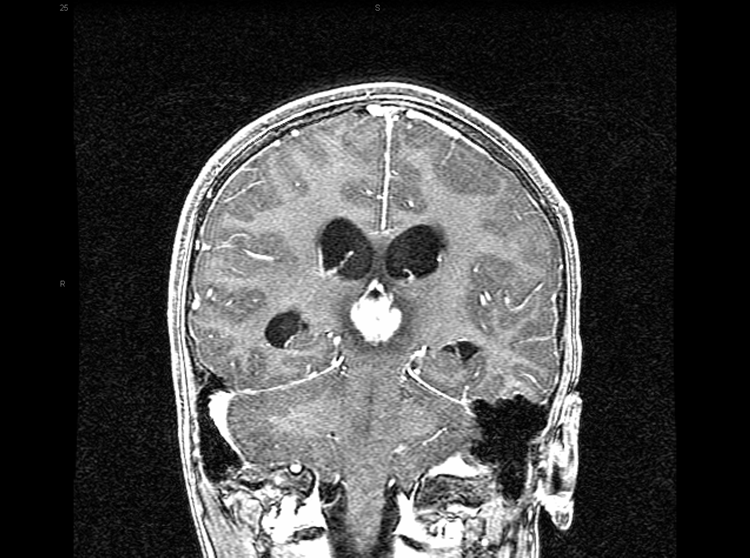

松果體瘤,由異常組織引起的松果體病變,常見于兒童和年輕人。松果瘤很少見。其中常見的是生殖細胞腫瘤(包括生殖瘤和畸胎瘤),其起源于生殖細胞(卵和精子細胞的前體)的胚胎殘留。生殖細胞腫瘤是惡性和浸潤性的,可能威脅生命。松果細胞的腫瘤(松果體的主要細胞類型)也會發(fā)生,并可能改變其惡性變化。

松果體瘤可引起頭痛、嘔吐,而且由于顱內(nèi)壓增加癲癇發(fā)作。一些患者可能由于性繼發(fā)性特征的退化而導(dǎo)致性腺功能減退,而另一些患者則可能由于人絨毛膜促性腺激素的分泌而早熟。尿崩癥的特征是口渴過度和尿液稀少,經(jīng)常出現(xiàn),通常是由于下丘腦的 腫瘤浸潤引起的。 垂體柄的入侵可能會干擾下丘腦中多巴胺對催乳素分泌的控制,從而導(dǎo)致血清催乳素濃度升高。治療一般包括手術(shù)和放射治療。

具體的并發(fā)癥與正常的松果體解剖及腫瘤組織學(xué)有關(guān),松果體區(qū)域的壓縮鄰近結(jié)構(gòu)的病變常常導(dǎo)致典型的臨床綜合征。常見的表現(xiàn)之一是導(dǎo)水管壓迫和導(dǎo)致的阻塞性腦積水引起的頭痛、惡心和嘔吐等。